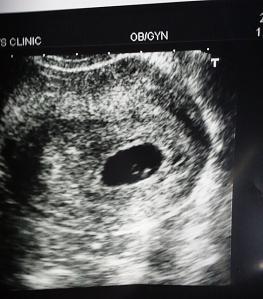

胎芽、心拍確認出来た時のエコー写真です。